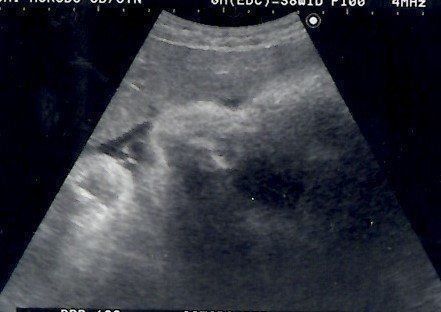

こぢんまり子さんの妊娠38週目のエコー写真 出産直前!

出産前日のエコーです。真ん中の薄い線が背骨、上のところが腰だと思います。この頃は、赤ちゃんの頭は私の骨盤の方にあり、顔を見ることはできませんでした。